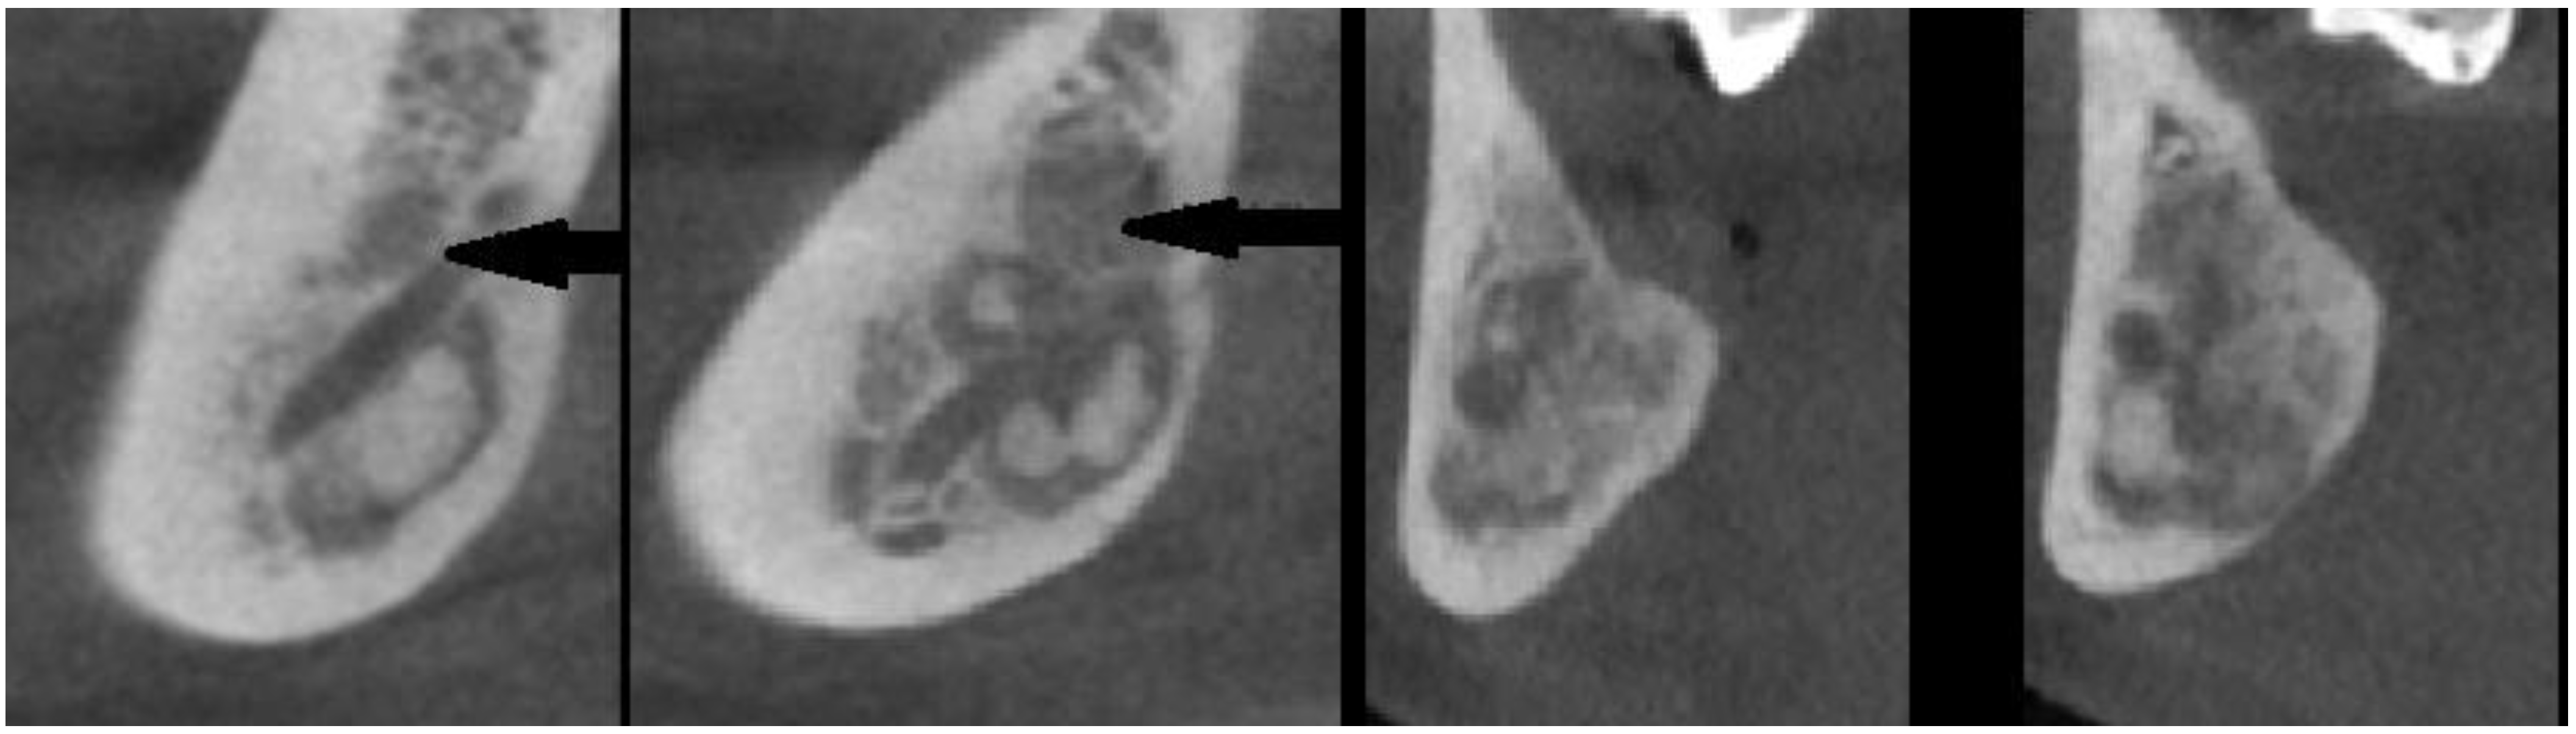

- various stages of calcifying masses inside of the lesion, Figure 5

- may cause cortical expansion or teeth displacement, Figure 5.